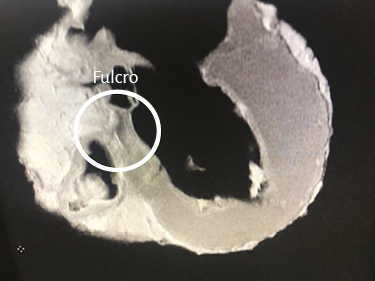

La maniobra clave para lograr el desenrollamiento miocárdico consiste en introducirse en el surco interventricular anterior (figura 20) en forma roma, lo cual permite dejar en el lado izquierdo del operador el extremo del miocardio que corresponde a la arteria pulmonar y a su contigüidad con la pared libre del ventrículo derecho (segmento derecho). A continuación se ejerce tracción hacia el mismo lado izquierdo, maniobra que deja a la arteria pulmonar totalmente liberada del resto del miocardio (figura 21). Esta disección del miocardio descubre al fulcro cardíaco por debajo y delante de la aorta, en una localización separada del trígono derecho y en un plano inferior al nacimiento de la arteria coronaria derecha, sin continuidad con la válvula aórtica e insertado como un elemento complementario entre la aorta y el miocardio (figuras 21, 31, 48, 49, 51 y 52) (205). Esta estructura, lugar de apoyo del extremo inicial y final del músculo cardíaco, constituye la inserción del miocardio de manera análoga a un músculo esquelético.

Al inicio del desplegamiento miocárdico lo primero que se interrumpe es un núcleo condroide, donde confluyen ambos extremos del miocardio y al cual hemos denominado fulcro cardíaco (211). Discontinuado este punto, se divorcian los extremos del miocardio. El segmento derecho (inicio) se amarra fundamentalmente a la superficie anterior del fulcro. El segmento ascendente, extremo final del miocardio, ingresa al fulcro fundamentalmente por la parte inferior (figuras 18, 21, 33 y 51). En esta maniobra el miocardio pierde la integridad. Desaparece su solidez integral. El sector del segmento derecho que se extiende desde el fulcro hasta la arteria pulmonar es el tronco pulmotricuspídeo simplemente adosado al segmento ascendente ubicado posteriormente (figuras 29 y 30).

Análisis histológico del fulcro cardíaco. En las investigaciones anatómicas hemos hallado en todos los corazones de bóvidos y de humanos un núcleo cuya estructura histológica es diferente de acuerdo con los especímenes analizados, presentándose como de carácter óseo, condroide o tendinoso. En esta estructura se amarran tanto las fibras musculares del segmento derecho (inserción inicial) como las del segmento ascendente (inserción final). Durante la disección del miocardio, el hallazgo en esta investigación del fulcro cardíaco como núcleo donde se inserta el miocardio nos condujo a otras indagaciones: ¿cuáles eran sus características?, ¿qué ubicación ostenta?, ¿cuál es la histología?, ¿es análoga su presencia en distintas especies?, ¿cómo se inserta el músculo miocárdico en dicha estructura que hemos denominado fulcro cardíaco?

Este sitio de inserción que hemos denominado fulcro cardíaco se encuentra en las proximidades de la válvula tricúspide (derecha), de la aorta (superior) y del cordón pulmotricuspídeo (anterior) (figuras 30 y 31). Para poder hallarlo es necesario desplazar hacia la izquierda del observador la arteria pulmonar y el segmento derecho, desnudando la raíz de la aorta. Este gesto descubre al fulcro por debajo de la aorta e inferior al trígono derecho, sin ninguna continuidad con este, por debajo del nacimiento de la arteria coronaria derecha, desprendido de la continuidad aórtica y ubicado como un elemento complementario entre aorta y miocardio (figura 21).

La existencia de una formación ósea, denominada os cordis, en bóvidos y ovejas es un hecho mencionado en ciencia veterinaria. Con posterioridad a nuestra primera publicación en 2018 sobre su hallazgo en el hombre (205), últimamente también fue ubicado en el chimpancé (109). En estas referencias es situada en el mismo sitio en el que nosotros hemos investigado esta estructura, tanto en bóvidos como humanos. Más allá de su mera alusión, hasta nuestras investigaciones nunca se le asignó ninguna función ni el sentido de su presencia, como asimismo careció de descripción en el ser humano (figuras 32 y 33) (216).

En bóvidos, la consistencia del fulcro cardíaco, óseo a la palpación (figuras 34 y 35), ha sido confirmada por la histología (figuras 36 a 38). Su tamaño, corroborado por disección (figura 39) y tomografía computada (figuras 58 y 59), es de aproximadamente 37 a 45 × 15 mm y de forma triangular. El análisis microscópico del fulcro cardíaco bovino muestra una matriz osteocondral trabecular con líneas segmentarias. Su estructura general asemeja al crecimiento metafisario de los huesos largos. A mayor aumento se pueden observar trabéculas óseas con osteoblastos y líneas segmentarias secundarias a aposición ósea. Los mismos hallazgos histológicos se han encontrado en chimpancés (109). La inserción secuencial de las fibras miocárdicas en el fulcro bovino se puede observar en las figuras 40-42.

Imágenes del fulcro cardíaco. Los corazones de bovino, estudiados con tomografía computada (figuras 58-60), resonancia magnética (figuras 61 y 62) y radiología simple (figura 63) evidenciaron el núcleo osteo-condroide hallado en la disección, observándose la misma morfología y tamaño análogo. En la tomografía humana hemos encontrado, en el análisis de la región donde se encuentra el fulcro cardíaco a través de las disecciones realizadas, la presencia de una intensidad en unidades Hounsfield por encima de 110 UH, mientras que el músculo adyacente tiene unidades por debajo de 80 UH. De esta manera, en la imagen, la estructura del fulcro alcanza un promedio de 132 ± 4,5 HU. En las áreas adyacentes, correspondiente al músculo miocárdico, este valor se ubicó entre 47,96 ± 12,5 y 77,59 ± 21,64 HU (figura 64).

Nuestras investigaciones han demostrado, en el trayecto del segmento septal del anillo aórtico que se extiende desde el trígono izquierdo al derecho, la presencia de un núcleo sólido que hemos denominado fulcro cardíaco (por debajo del origen de la arteria coronaria derecha), donde se amarra el miocardio continuo en su inicio y al final, que como todo músculo necesita un apoyo para cumplir con su función.